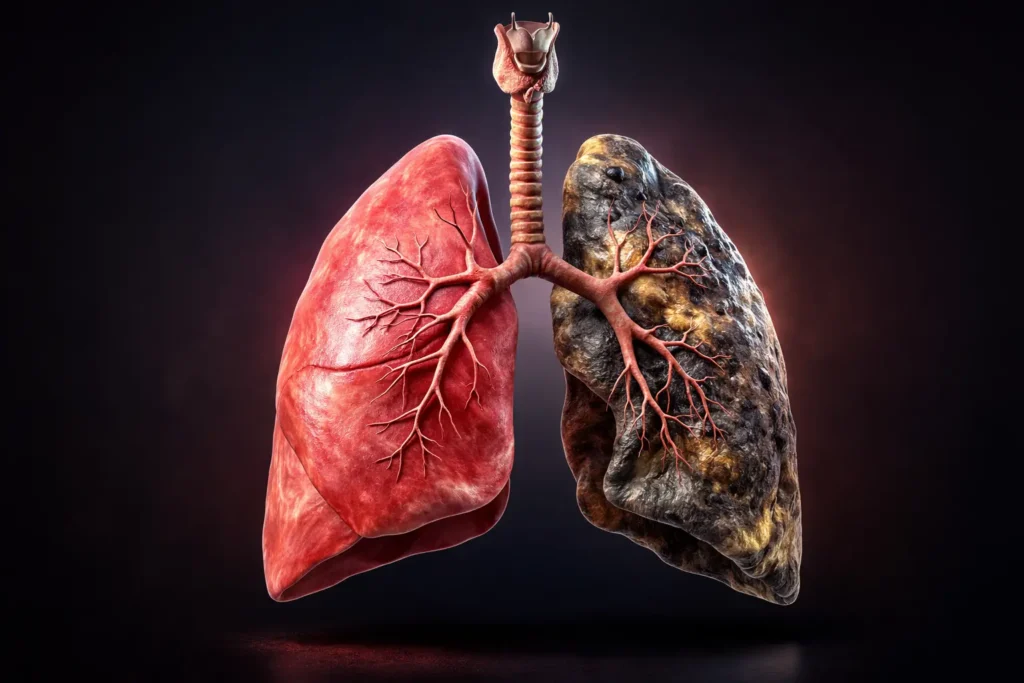

The question “Do genes decide lung cancer in smokers?” is one of the most important and misunderstood topics in modern healthcare. While smoking remains the leading cause of lung cancer, not all smokers develop the disease. This raises a critical question: why do some individuals get lung cancer while others do not?

The answer lies in a combination of genetic predisposition and environmental exposure. Genes do not directly “decide” outcomes, but they significantly influence how the body responds to harmful substances like tobacco smoke.

However, a surprising number of lifelong smokers never develop lung cancer, while some non-smokers do. This variation highlights the importance of understanding genetic risk factors.

Role of Carcinogens in Tobacco Smoke

Cigarette smoke contains over 7,000 chemicals, many of which are carcinogens. These substances damage DNA in lung cells.

This means two smokers with similar habits may have very different risks.

So, do genes decide lung cancer in smokers? The answer is no—but they play a significant role. Smoking remains the primary risk factor, but genetics influence how the body reacts to that exposure.